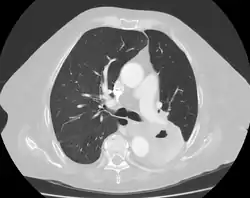

Cavitation of a lung squamous carcinoma, infrahilar, affecting the left lower lobe. 72-year-old woman.

The most common cause of a single lung cavity is lung cancer.[4] Usually, the cavity forms because the cancer grows more rapidly than its blood supply, resulting in necrosis (cell death) in the central part of the cancer. 81% of lung cancers that develop cavities over-express epidermal growth factor receptor (EGFR), which could be related to rapid growth, central necrosis, and cavity formation.[11] 11% of primary lung cancers (cancers that start in the lung) have cavities that can be seen on chest X-ray; 22% of primary lung cancers will have cavities on CT, which is more sensitive.[2] Squamous-cell carcinoma of the lung is more likely to develop cavitations than lung adenocarcinoma or large-cell lung carcinoma.[2] Other primary cancers of the lung, such as lymphoma and Kaposi’s sarcoma, can also cavitate, especially in people with AIDS.[7] Lung cancers that develop cavities are associated with a poor prognosis (worse outcomes). Cancers that metastasize (spread) to the lung can also develop cavitations, but this is only seen about 4% of the time on X-ray. Metastatic cancers of squamous cell origin are also more likely to cavitate than cancers of other origins.[7] Both chemotherapy (drugs to treat cancer) and radiofrequency ablation (destroying cancer with radio waves) can cause lung cancers to develop cavities, which is a sign of a good response to treatment.[2] It is possible to have both an infection and lung cancer in the same cavity; the most common combination is primary lung cancer and tuberculosis.[7]